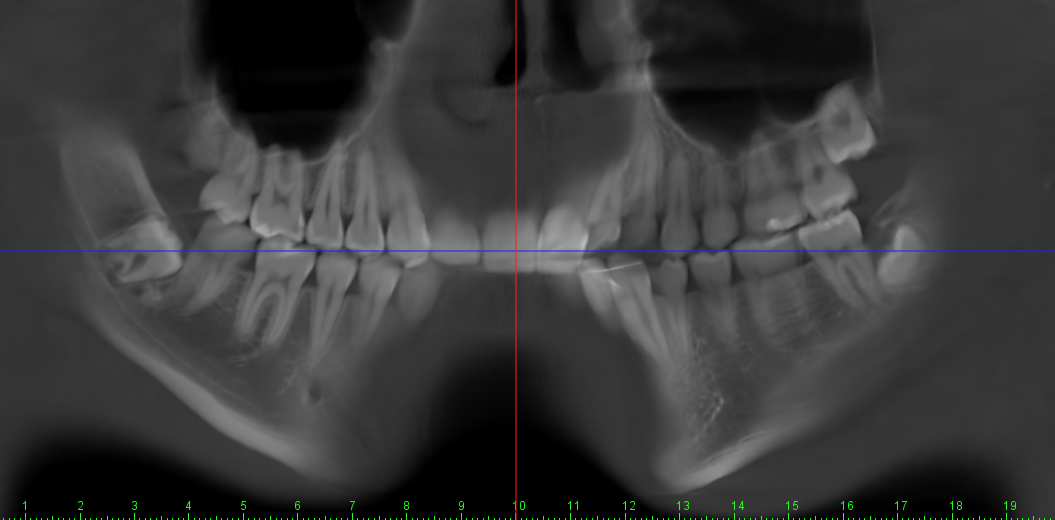

My jaw surgery movements are limited because of my natural unfortunate teeth position and a combination of other factors.

I have what some asian surgeons describe as a “protruding mouth.” However that type of protrusion is often related to the shape of the maxilla and is typically addressed by removing a portion of the maxilla, often together with tooth extractions which is very fucking dumb.

My jaw surgery movements are limited because of my natural unfortunate teeth position and a combination of other factors.

I have what some asian surgeons describe as a “protruding mouth.” However that type of protrusion is often related to the shape of the maxilla and is typically addressed by removing a portion of the maxilla, often together with tooth extractions which is very fucking dumb.

At least 4* of counter clockwise rotation on both jaws.

5mm+ advancement on both maxilla and mandible

At least 4* of counter clockwise rotation on both jaws.

5mm+ advancement on both maxilla and mandible